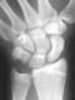

Microfracture

Microfracture surgery is an articular cartilage repair surgical technique that works by creating tiny fractures in the underlying bone. This causes new cartilage to develop from a so-called super-clot. [Source: Wikipedia ]